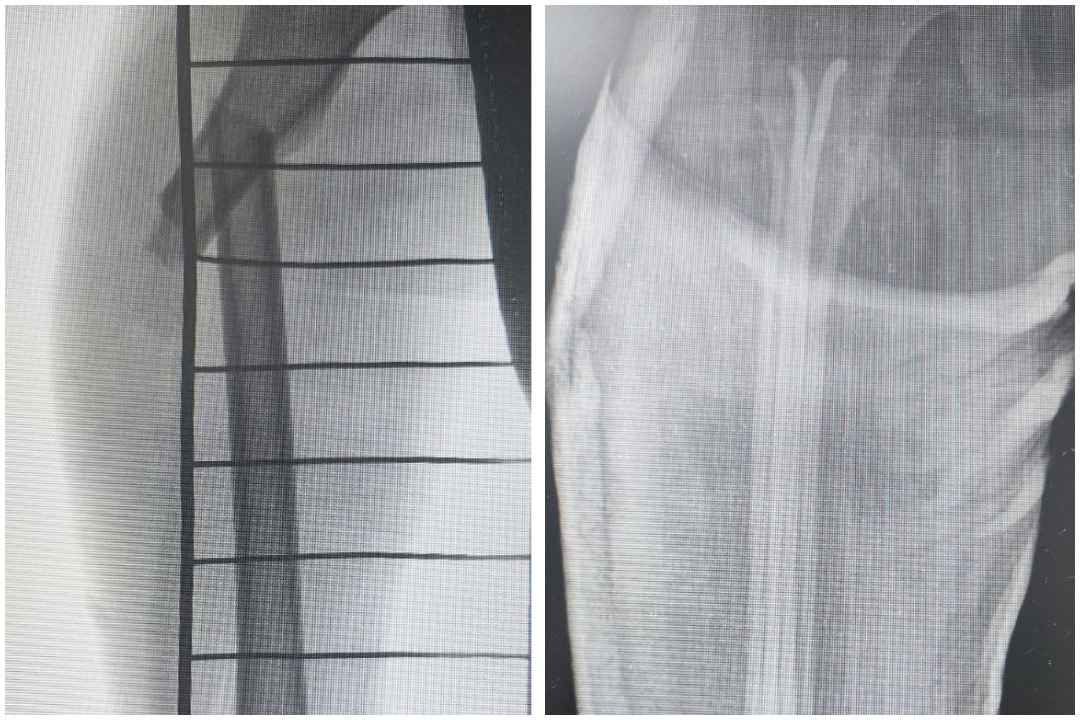

У мальчика закрытый перелом бедренной кости со смещением. Экстренная операция была проведена успешно. Сейчас маленький пациент получает необходимое лечение в отделении травматологии и ортопедии. На сращение перелома уйдет примерно 5-6 недель.

Фото: Детская Республиканская клиническая больница